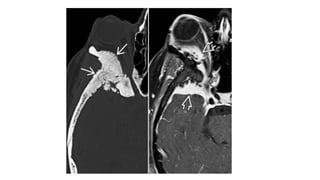

• Multiplaner sagital ,coronal and axial images show a well defined ,midline, broad dural based,

lobulated T1WI iso , T2WI iso to slightly hyper and FlAIR hyperintense mass noted in suprasellar

area having extension forwards along the planum sphenoidale and backwards along the dorsum

sellae.

• After IV contrast avidly homogenous enhancement of the lesion and adjacent linear dural

enhancement over the clivus and planum sphenoidale representing dural tail are noted.

• The lesion causing compression over the optic chiasma, pituitary gland and floor of 3rd ventricle,

and encasing the supraclinoid ICA, ACA and MCA of both sides.

• The mass effect is evidenced by obliteration of Suprasellar & interpeduncular cysterns and

symmetrical indentation of underlying cerebral cortex.

• No perilsional edema is noted

• However lateral , 3rd and 4rth ventricles appear normal

• Complementary CT cut was taken and showing iso to slightly hyperdense lesion. No calcification is

noted. Bone CT shows bony hyperostosis at planum sphenoidale .Sellar size is within normal limit